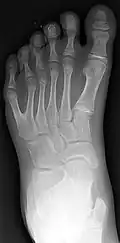

Classification is performed by using x-ray imaging to see the bone structures.[17] In 1961, Frantz and O'Rahilly proposed that congenital anomalies of the limb could be classified in seven categories, based on the embryonic failure causing the clinical presentation. These categories are failure of formation of parts, failure of differentiation, duplication, overgrowth, undergrowth, congenital constriction band syndrome, and generalized skeletal abnormalities.[36] In 1976 this was modified by Swanson.[37] Polydactyly belongs to the category of duplication.[12] As of 2009, research has shown that the majority of congenital anomalies occur during the 4-week embryologic period of rapid limb development.[12]

X-ray of type III central polydactyly. The middle fingers are the same length. -